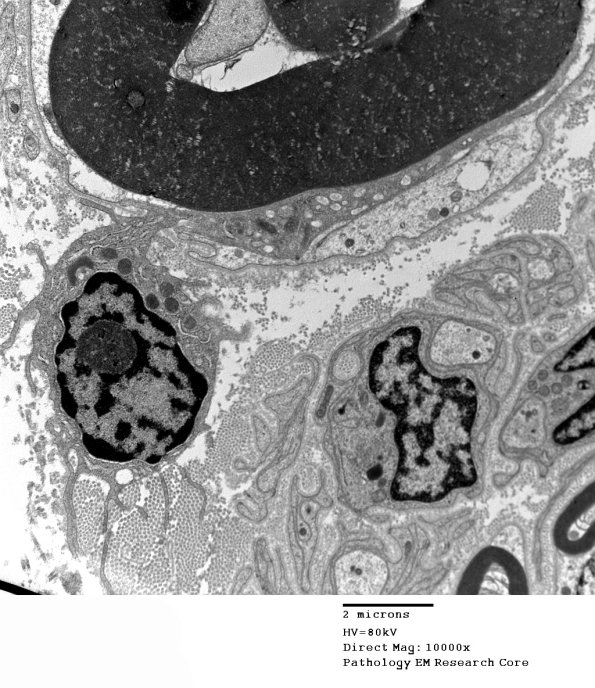

1D1-26 I know that I have illustrated this section excessively. Macrophage-mediated demyelination has always been one of my favorite nerve pathologies. Each numeral is a different axon in this case with higher magnification images of that axon designated A,B,C….---- 1D1A-D A very busy endoneurium in this nerve with numerous macrophages, particularly involving the axon in the left lower corner seen subsequently at several magnifications. (electron micrographs)